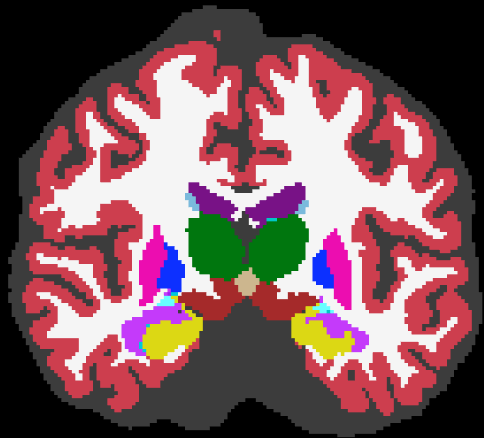

(a) MPRAGE

(b) ASEG

(c) MALF

(d) PSACNN

(e) Manual

(f) SAMSEG

(g) CNN

In this experiment we compare the performance of segmentation algorithms on test data with the exact same acquisition parameters as the training data. The test data consists of 20 subject MPRAGEs from the Buckner data that are independent of the 16 subjects used for training and 3 for validation of the CNN methods.

Figure 5 shows an example input test subject image, its manual segmentation, and segmentations of the various algorithms. All algorithms perform reasonably well on this dataset. We calculated the Dice coefficients of the labeled structures for all the algorithms (see Fig. 6). From the Dice coefficient boxplots (generated from 20 subjects) shown in Fig. 6 we observe that CNN (red) and PSACNN (blue) Dice overlap (ALL Dice ) is comparable to each other and is significantly better (paired t-test ) than ASEG (green), SAMSEG (yellow), and MALF (purple) for many of the subcortical structures, and especially for whole white matter (WM) and gray matter cortex (CT) labels. This suggests that large patch-based CNN methods do provide a more accurate segmentation than state-of-the-art approaches like MALF and SAMSEG for a majority of the labeled structures. But, since the training and test acquisition parameters are exactly same, there is no significant difference between CNN and PSACNN.